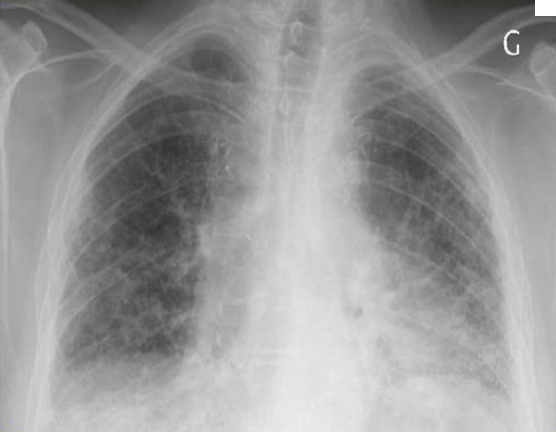

Un scanner thoracique a été réalisé.

Figure 5.

Question 7 - Quelle(s) anomalie(s) constatez-vous (une ou plusieurs réponses exactes) ?

Il s’agit ici d’un tableau de pneumopathie interstitielle diffuse avec un pattern de fibrose. La sémiologie des lésions élémentaires du syndrome interstitiel déjà décrit à la question 2 est associée à des signes de fibrose qui peuvent comprendre de manière générale deux grandes entités :

1) de la destruction parenchymateuse : typiquement les microkystes (rayon de miel) qui sont de petits « trous », avec paroi, à prédominance sous-pleurale ;

2) des distorsions architecturales dont la plus connue et fréquente est la bronchectasie de traction (différent de la dilatation des bronches qui est une maladie inflammatoire des bronches, la bronchectasie de traction correspond juste à une distorsion de la bronche par traction interstitielle).

Concernant l’origine de la PID, l’on s’orientera ici préférentiellement vers l’asbestose, car le scanner montre des images qui sont plutôt en faveur de pneumopathie interstitielle commune (PIC) (absence de verre dépoli), et l’alvéolite est neutrophilique. Dans le cadre d’une PID médicamenteuse, l’alvéolite est plutôt lymphocytaire, voire éosinophilique, et les images sont plutôt en faveur d’une pneumopathie interstitielle non spécifique (PINS) (verre dépoli +++). Enfin, si l’alvéolite est plutôt neutrophilique ou lymphocytaire dans la PID de la dermatopolymyosite, le scanner montre le plus souvent des images de pneumopathie interstitielle non spécifique (PINS).

La PIC et la PINS sont des tableaux radiologiques décrits ci-dessous.